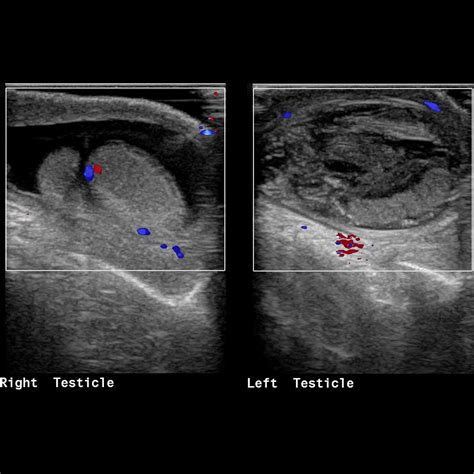

Premium Photo | Ultrasound of kidneys and doctor analyzes condition of

Premium Photo | Ultrasound of kidneys and doctor analyzes condition of ...